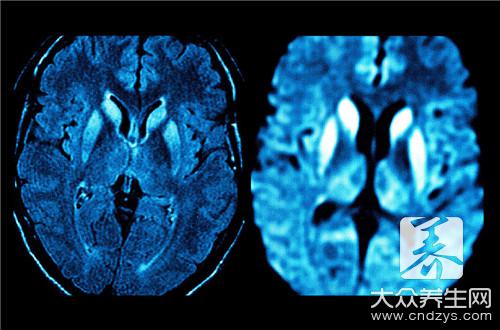

4、四期(昏迷期) 神志完全丧失,不能唤醒。浅昏迷时,对痛刺激和不适体位尚有反应,腱反射和肌张力仍亢进;扑翼样震颤无法引出。深昏迷时,各种反射消失,肌张力降低,瞳孔常散大,可出现阵发性惊厥、踝阵挛和换气过度。脑电图明显异常。

对于文章介绍的老年人肝性脑病这种常见的老年人疾病,它对于老年人的肝脏和大脑的影响是比较大,而且老年本身的器官功能就开始出现衰减,所以这种疾病会加快器官的老化,对于患者的身体健康是影响比较大的,希望你们可以重视。